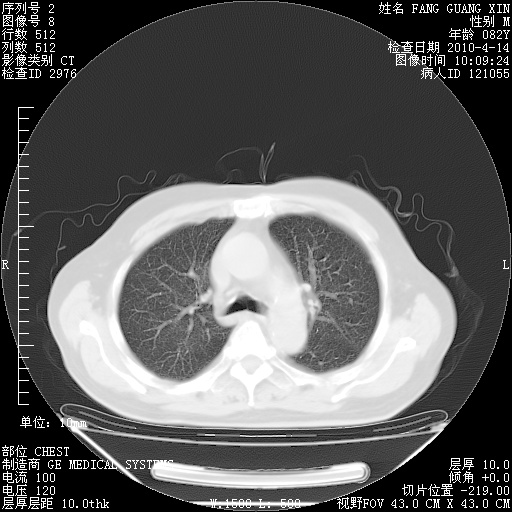

4月14日肺部CT

23.JPG

24.JPG

25.JPG

26.JPG